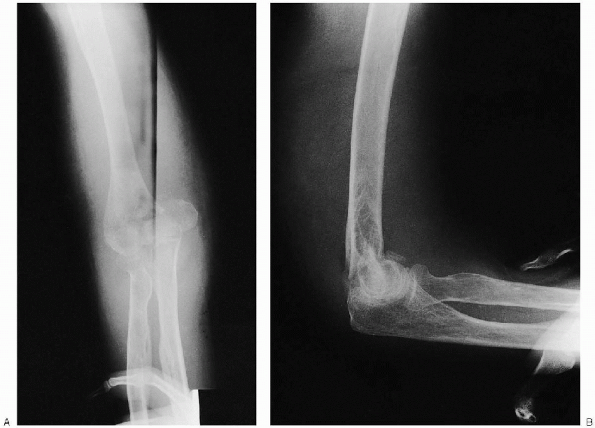

FIGURE 10-4. Anteroposterior (A) and lateral (B) radiographs demonstrating a displaced intraarticular distal humerus fracture.